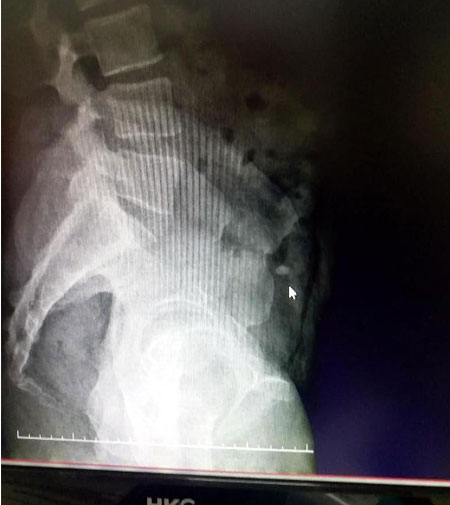

ULTRASINDA TESBİT EDİLDİ

İsminin açıklanmasını istemeyen kuyumcu ise, "Pırlanta 2.5 kırat ağırlığında ve piyasaya satış değeri 40 bin dolardır. Şu anda çalan turistin bağırsağında olduğu ultrasonda tespit edildi. Bir an önce pırlantanın çıkarılmasını bekliyorum. Şikayetçiyim" dedi.